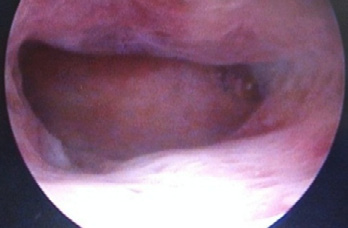

Dos meses después, la paciente consultó con ciclos regulares normales, manifestando interés en un nuevo embarazo y preocupación por la posibilidad de adherencias u otra alteración endometrial residual, producto de su cuadro clínico reciente, además de su antecedente de aborto espontáneo en el primer embarazo, que también ameritó legrado cuando cursaba 23 semanas; por todo lo anterior, se propuso realizar histeroscopia, la cual se practicó sin complicaciones, en fase folicular del ciclo, con técnica oficinal, encontrando cavidad de aspecto normal, ambos ostium vistos (figura 4).

Figura 4. Fotografías de fondo uterino y ambos ostiums Fuente: archivo personal del autor, con autorización de la paciente.